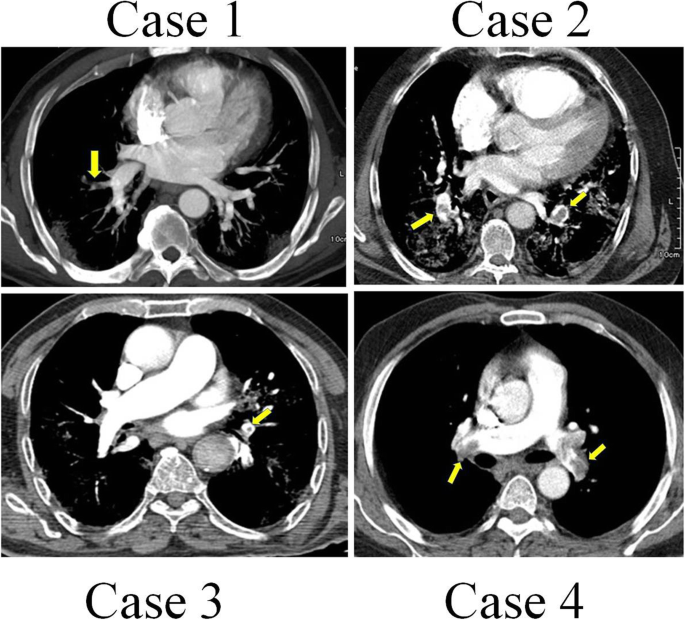

A 60-year-old man was presented to the medical unit in July 2020 with symptoms of respiratory problems, severe headache, cough, dizziness, and frequent vomiting. Initial physical and clinical examinations of the patient were normal and there was no underlying disease. The patient had no history of alcohol or tobacco use and was not taking any specific medications at the time. His blood pressure was 120/80 mmHg with a regular pulse rate of 112 beats/min, a respiratory rate of 22 cycles/min, and a temperature of 36 °C. While the patient had no symptoms of arrhythmia, he had mild hypoxemia with an oxygen level of 85–92% (Table 1). Important laboratory findings of the patient are listed in Table 2. PCR on the nasopharyngeal swab sample was performed on the day of hospitalization, which confirmed the diagnosis of COVID-19. The patient was discharged from the hospital after 2 days because his symptoms were relatively mild and there were no other serious symptoms. He was admitted to the hospital 5 days later with respiratory problems, and initial examinations revealed that his oxygen saturation was then 82% on room air. The patient underwent high-resolution computed tomography (CT) scans of the lungs and CT pulmonary angiography. CT scans of the lungs (Fig. 1) showed several diffuse areas of opacity in both right and left lungs, which could indicate viral pneumonia. In addition, on CT angiography of the lungs (Fig. 2), several filling defects were visible in the branch of the pulmonary artery leading to the lower lobe of the right lung, which may indicate acute pulmonary embolism. The patient was started on medications including naproxen to control the muscle pain, hydroxychloroquine and famotidine with antiviral effects, zinc to boost the immune system and repair lung tissue, and neurobion to strengthen the immune system. Some anticoagulant including injected heparin and acetylsalicylic acid tablets, and high-flow oxygen were also used. The severity of COVID-19 in this patient was moderate and he did not require mechanical ventilation or intensive care unit (ICU) management and was released from the hospital 15 days after partial recovery.

A 56-year-old man was hospitalized in November 2020 due to the persistence of high fever that started 5 days before. In physical and clinical examinations of the patient, symptoms such as fever, chills, muscle pain, weakness, cough, tachycardia, and acute respiratory syndrome were reported, while there was no report of underlying disease in the patient’s file. Investigations showed no history of alcohol and tobacco intake or any particular medication use at the time. A polymerase chain reaction (PCR)-based test for SARS-CoV-2 was done, and he was diagnosed with COVID-19. Initial examinations of the patient in the hospital revealed a blood pressure of 130/90 mmHg with a regular pulse rate of 109 beats/min, a respiratory rate of 28 cycles/min, and a temperature of 39 °C (Table 1). All laboratory findings of the patient are presented in Table 2. The patient’s electrocardiography (ECG) was normal. There were no changes in the patient’s hemodynamics or respiratory status (oxygen saturation: 84% on room air), and in later stages, due to persistent respiratory problems, CT pulmonary angiography of the patient was ordered by a pulmonologist for further examination. As in CT angiography (Figs. 1 and 2): (a) the diameters of the main pulmonary arteries were normal; (b) defective filling in the lobar, segmental, and sub-segmental branches of the upper, middle, and lower lobes was evident in both lungs, which may indicate thrombosis (embolism); and (c) multiple confluent patchy ground-glass opacification (GGO) and consolidation was found in both lungs. Due to the positive result of COVID-19 test and all the other symptoms mentioned above, the COVID-19 diagnosis was confirmed with a moderate severity. No deep vein thrombosis or other thrombosis were detected. Continuous heparin injection was performed according to the doctor’s instructions to treat pulmonary embolism. Supportive care, antibiotics, and other treatments were used to treat the patient, and he eventually was discharged after 18 days of hospitalization.

A 95-year-old male patient with a history of severe dyspnea for 2 days was referred to a medical center in November 2020. Examination of the patient’s file showed that he had experienced several episodes of diarrhea a few days prior to the onset of shortness of breath, which resolved on its own. According to the patient’s history, his wife had contracted coronavirus 2 weeks before. The examinations also showed that the patient had symptoms of fever, cough, and chest pain. His previous medical history showed low blood pressure and hyperlipidemia, but no history of malignancy. Examination of the family history revealed no signs of coagulation disorders or thromboembolism. The patient never smoked or consumed alcohol. His vital signs included blood pressure of 100/65 mmHg, pulse rate of 88 beats/min, respiratory rate of 60/min, oximetry 76% on room air, and a temperature of 38.5 °C (Table 1). There was no lower extremity edema or calf tenderness. The most common blood and electrolyte tests are listed in Table 2. Testing for viral diseases, including influenza was negative. The initial results of the coronavirus test were negative, but in the second test, which was taken from back of the throat, the coronavirus was detected. According to the patient’s respiratory rate and old age, a CT scan of the lung was performed on the order of the treating physician, and CT images showed a specific sign of the virus (Fig. 1). Due to the deterioration of the patient and having respiratory problems, he was transferred to the hospital’s ICU, approximately 4 days after hospitalization. CT pulmonary angiography was also performed by the order of a pulmonologist. As shown in the CT scan images of the patient, there is a defect of contrast material in the middle lobe branch of the left pulmonary artery, which can indicate chronic thrombosis in this artery (Fig. 2). The patient was started on naproxen, hydroxychloroquine, famotidine, zinc, neurobion, and anticoagulant treatments. Unfortunately, his COVID-19 was severe, and he died due to respiratory failure and intubation after 15 days of hospitalization in the ICU.

A 72-year-old man was hospitalized in a hospital in Sanandaj, Iran in December 2020 after 11 days of cough, fever, weakness, palpitation, and respiratory problems, but no chest pain. The COVID-19 nucleic acid diagnostic test was positive before hospitalization. The severity of his disease was categorized as moderate and the patient was transferred to the quarantine ward of the hospital. At the time of admission, his clinical and physical examination did not show any irregularity in heartbeat, which could be a sign of atrial fibrillation. Other vital symptoms were blood pressure of 95/62 mmHg, temperature of 39 °C, respiration rate of 23 cycles/min, and oxygen saturation rate of 87%. After admission, the laboratory test of COVID-19 was re-confirmed in the hospital (Table 1). Unfortunately, we did not have access to the results of the routine blood tests and the patient’s serum biochemical analyses. Due to respiratory problems, CT angiography of the pulmonary arteries was ordered by his doctor. A defect of filling in the right and left main pulmonary arteries as well as the lobar and segmental branches of both sides was quite obvious (Figs. 1 and 2), which suggested pulmonary embolism. Examination of the lung parenchyma tissue also revealed multifocal turbidity in both lungs, which indicated infection. According to these findings, antiviral, antibacterial, anticoagulant, symptomatic and supportive treatments were started for the patient. Fortunately, with proper and timely treatment, the patient was discharged from the hospital 12 days after admission and the rest of the treatment was continued at home.